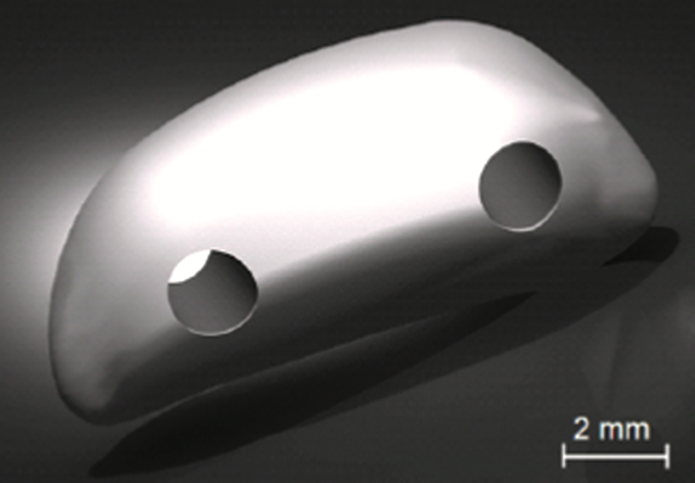

To help Oreo, OIC obtained a donated patella that was used to generate a scaled digitized copy. A biomedical engineer then converted the file into a computer-aided design (CAD) model. X-ray radiographs of Oreo’s other patella were then used to modify the CAD design to match his femur.

OIC built an artificial patella using FDM® technology, an additive manufacturing process that builds plastic parts layer-by-layer from CAD files, on its Stratasys® 3D printer using PC-ISO™ biocompatible polycarbonate (ISO 10993 USP Class VI). Physical testing was performed on the implant to validate its ability to provide the necessary mechanical strength. The implant was sterilized using ethylene oxide at 54°C (130°F) for one hour. During Oreo’s surgery, the implant was attached to the tendon and quadriceps using polypropylene sutures.